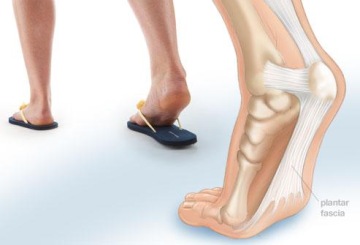

- Patní ostruhy

PATNÍ OSTRUHY

Z výše uvedených důvodů se také mohou vytvořit takzvané „patní ostruhy“. Zde se jedná buď o zánět vazového úponu, nebo o narušení patní kosti v místě kde přirůstají šlachy k patní kosti. Ošetření rázovou vlnou, nebo ultrazvukem řeší pouze následek a ne příčinu vzniku patní ostruhy.